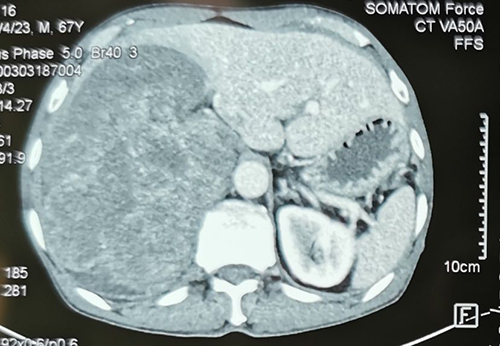

肿瘤CT表现

患者为男性,67岁,右侧腰部疼痛、胸闷1月余。泌尿外科主任吕家驹在接诊这位由胸外科专家介绍来的患者时非常吃惊,这是一例临床上很少见的巨大右侧腹膜后间叶源性肿瘤,最大长径超过30cm,肿瘤约1/2突入胸腔,与右侧肾脏、肝脏、大血管、脊柱关系密切。

吕家驹主任在切除肿瘤后进行检查,发现肿瘤最大长径35cm,重量达4200克,是临床上少见的巨大腹膜后肿瘤。